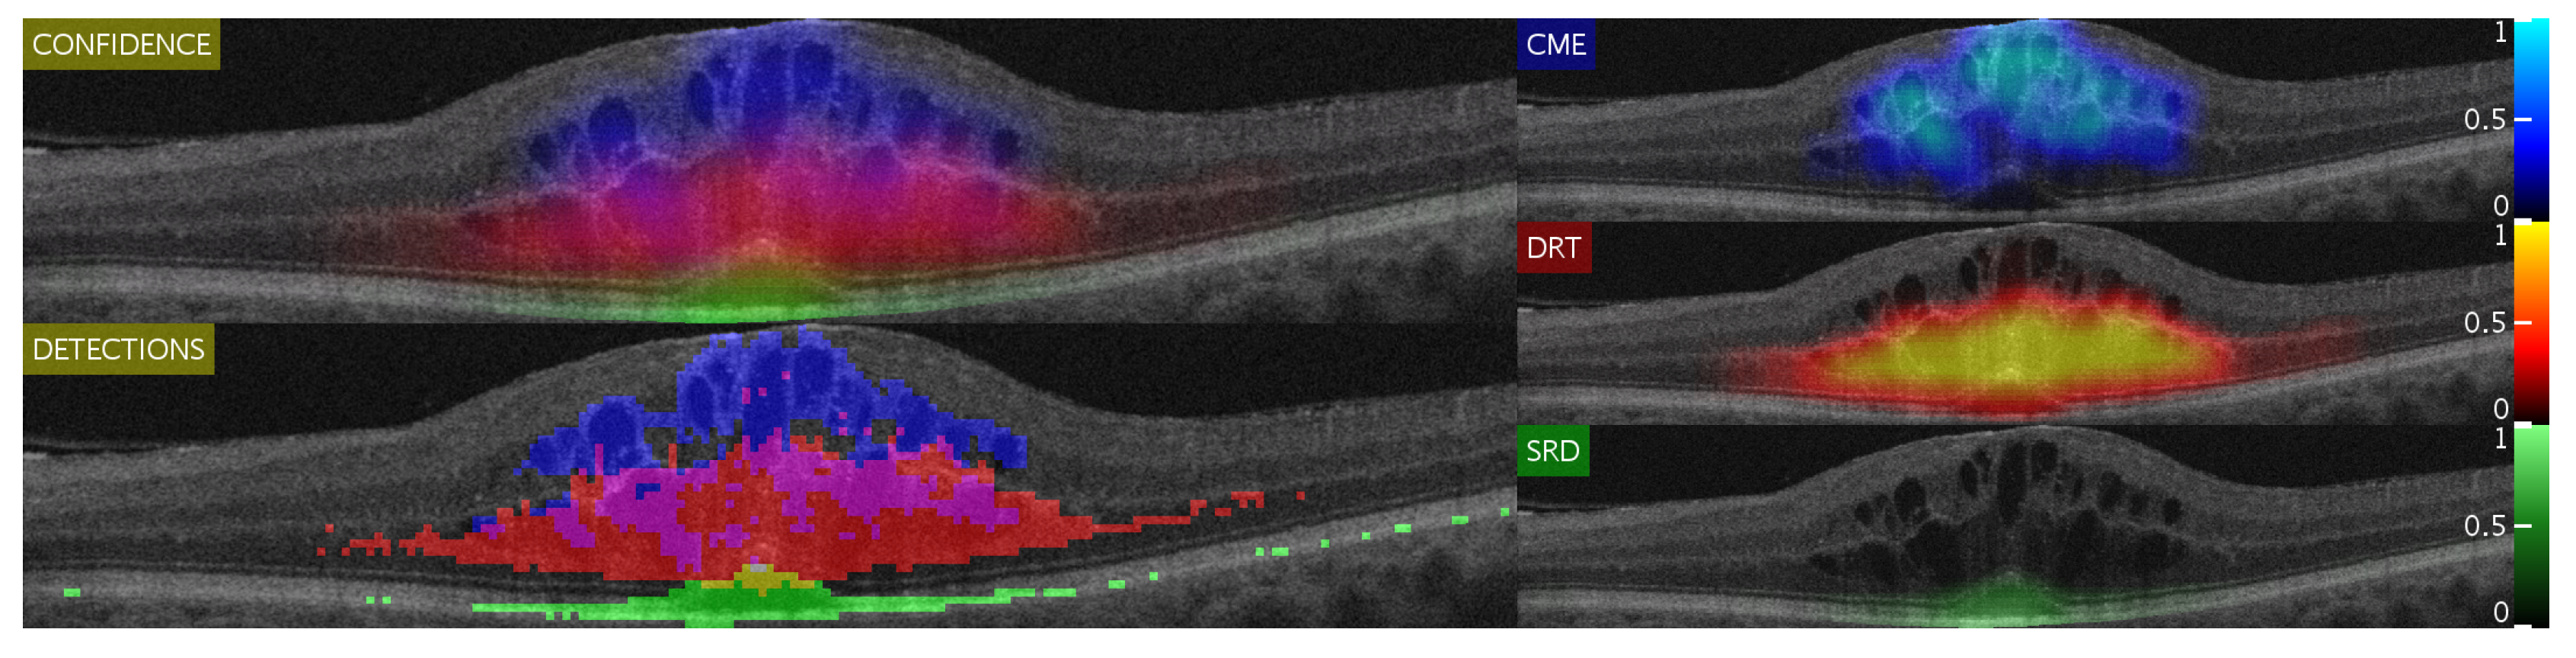

Figure 14 and Figure 15 show representative examples from the test set with a healthy image and another one with different types of pathological fluid generated with the Spectralis and Cirrus devices, respectively. In addition, the labels of the expert are included to compare with the results. As can be seen, in both cases, the system is capable of satisfactorily detecting the pathological fluid accumulations whenever they are present, although we can see spurious detections in the cases of both Figure 14a and Figure 15a. However, these detections can be easily corrected with post-processing strategies as mentioned before, but we decided to include them for a better understanding of the behavior of the system.

Figure 15.

Test visualizations generated using images from the Cirrus device.

In these visualizations, we can observe two major phenomena. The first one consists in the tendency to spurious detections in the images generated by the Spectralis of the SRD-type edema. This may be due to the higher contrast of the images generated by this device, favouring the appearance of common patterns of the SRD-type edema not present in the images that are generated with Cirrus. On the other hand, we can see a clear tendency in the Cirrus images to generate small detections of DRT-type edema. This is due to what was already mentioned in the section where we analyzed the selection of features: the DRT pattern of the images that are generated with the Cirrus device is very similar to the normal tissue in comparison with the "wet" and coarse texture of the DRT fluid accumulations in images that are generated with the Spectralis device.